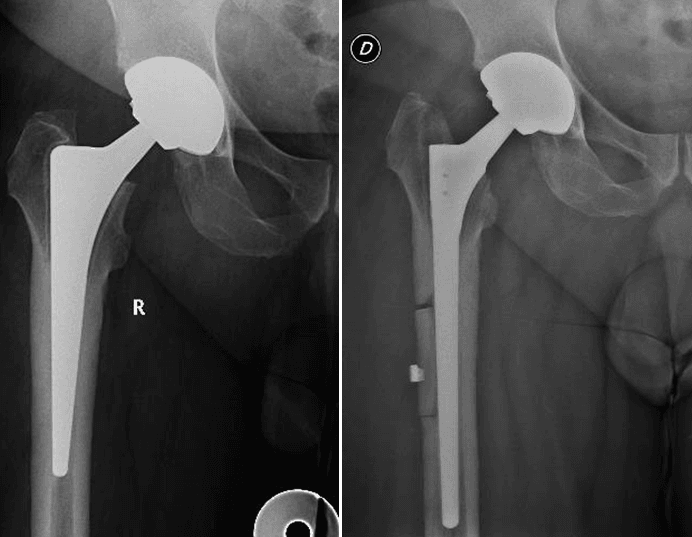

L’intervento chirurgico di revisione protesica si attua nel caso di fallimento dell’impianto primario. La revisione può essere totale (quando vengono sostituite tutte le componenti) o parziale (quando vengono sostituite solo alcune componenti), a seconda dell’entità e del tipo di problema riscontrato.

- Frattura peri-protesica

La revisione protesica rappresenta una vera e propria sfida per il Chirurgo Ortopedico, soprattutto in quei casi gravati da importante perdita del bone stock, da deficit dei tessuti molli periarticolari o in presenza di alterazioni del trofismo cutaneo, talvolta con perdita severa di sostanza, in esiti di plurimi interventi chirurgici.

L’esperienza e l’approccio del nostro centro

Grazie ad un’esperienza chirurgica decennale nel trattamento e nella gestione di casi difficili di revisione protesica, presso il nostro centro di Chirurgia Protesica pianifichiamo accuratamente gli interventi ricostruttivi protesici, avvalendoci delle più innovative tecniche e metodiche chirurgiche (impianti protesici su misura quando necessari), ponendo particolare attenzione nell’utilizzo di materiali protesici biocompatibili che garantiscono un’ottimale osteointegrazione ed una resistenza all’usura sempre maggiore.